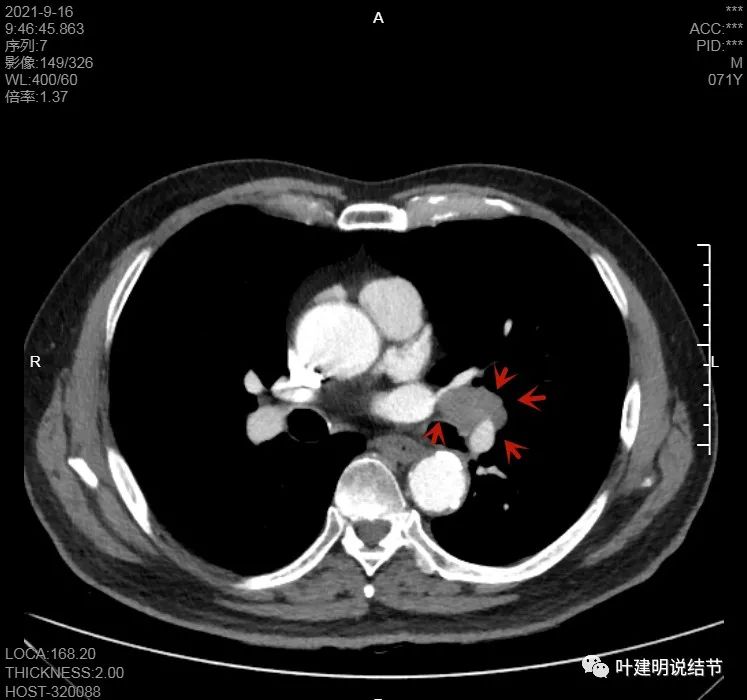

淋巴结巨大,部分包绕肺血管,但仍未见明显侵犯血管壁

肺血管受压明显,气管内壁感觉也是光滑的

以上诸图均示肿大淋巴结挤压肺血管,但未见确切侵犯破坏,支气管内壁也感觉是光滑的,没有肿瘤突向管腔

这样质地不硬,缺乏收缩力的原发灶,实性的,但却有明显的淋巴结转移,我首先想到的是小细胞肺癌,但小细胞肺癌容易广泛的纵隔淋巴结转移而且融合成团,这个病例只有肺门区的肿大淋巴结,不是特别符合。另外一个就是类癌,不典型类癌可以质软,缺乏破坏力,但却是恶性的,会转移。